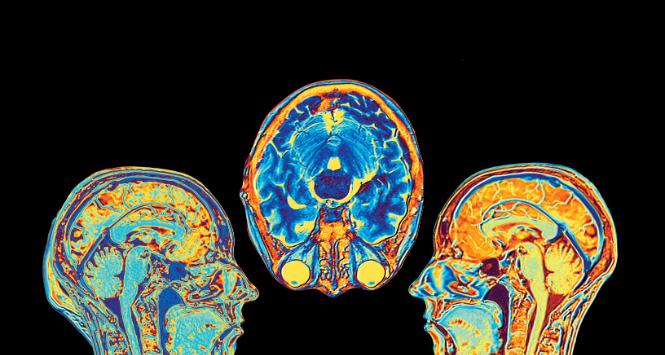

mózg